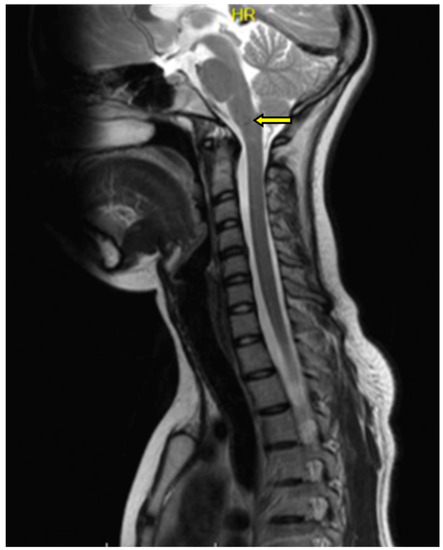

2. A Case Report

- -

- within the right thalamus (transverse dimensions of approx. 6 × 3.5 mm), with hemosiderin deposits,

- at the fronto-parietal junction on the right side in the subcortical location (transverse dimensions of approx. 3 × 5 mm),

- in the semioval center on the left side (transverse dimensions of approx. 7 × 4 mm),

- within the left occipital lobe (transverse dimensions of approx. 10 × 6 mm),

- in the right temporal lobe (transverse dimensions of approx. 7 × 3 mm and approx. 8 × 5 mm),

- in the area of the right frontal lobe (transverse dimensions of approx. 10 × 6 mm).